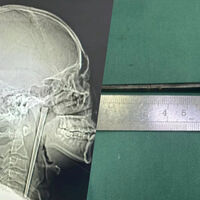

В китайском городе Далянь 46-летнего мужчину срочно доставили в больницу с сильной болью в горле. Во время обследования врачи нашли в его горле металлическую палочку длиной около 12 сантиметров, с которой пациент прожил восемь лет, пишет Mothership.

Обследование показало, что металлическая палочка застряла в задней части горла, при этом около трех сантиметров предмета выступали вверх. Несмотря на длительное пребывание инородного тела, врачи не обнаружили значительных кровотечений или язв.

Медики провели минимально инвазивную операцию и смогли извлечь палочку через рот, не прибегая к разрезу шеи.